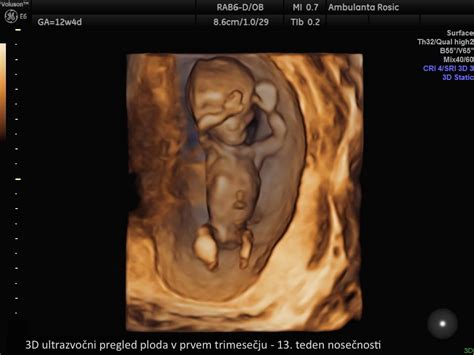

- Ultrazvočni pregled morfologije ploda: Izvede se okoli 20. tedna nosečnosti in omogoča natančen pregled razvoja vseh organov in struktur ploda. Pogosto je to tudi priložnost, da izveste spol otroka.